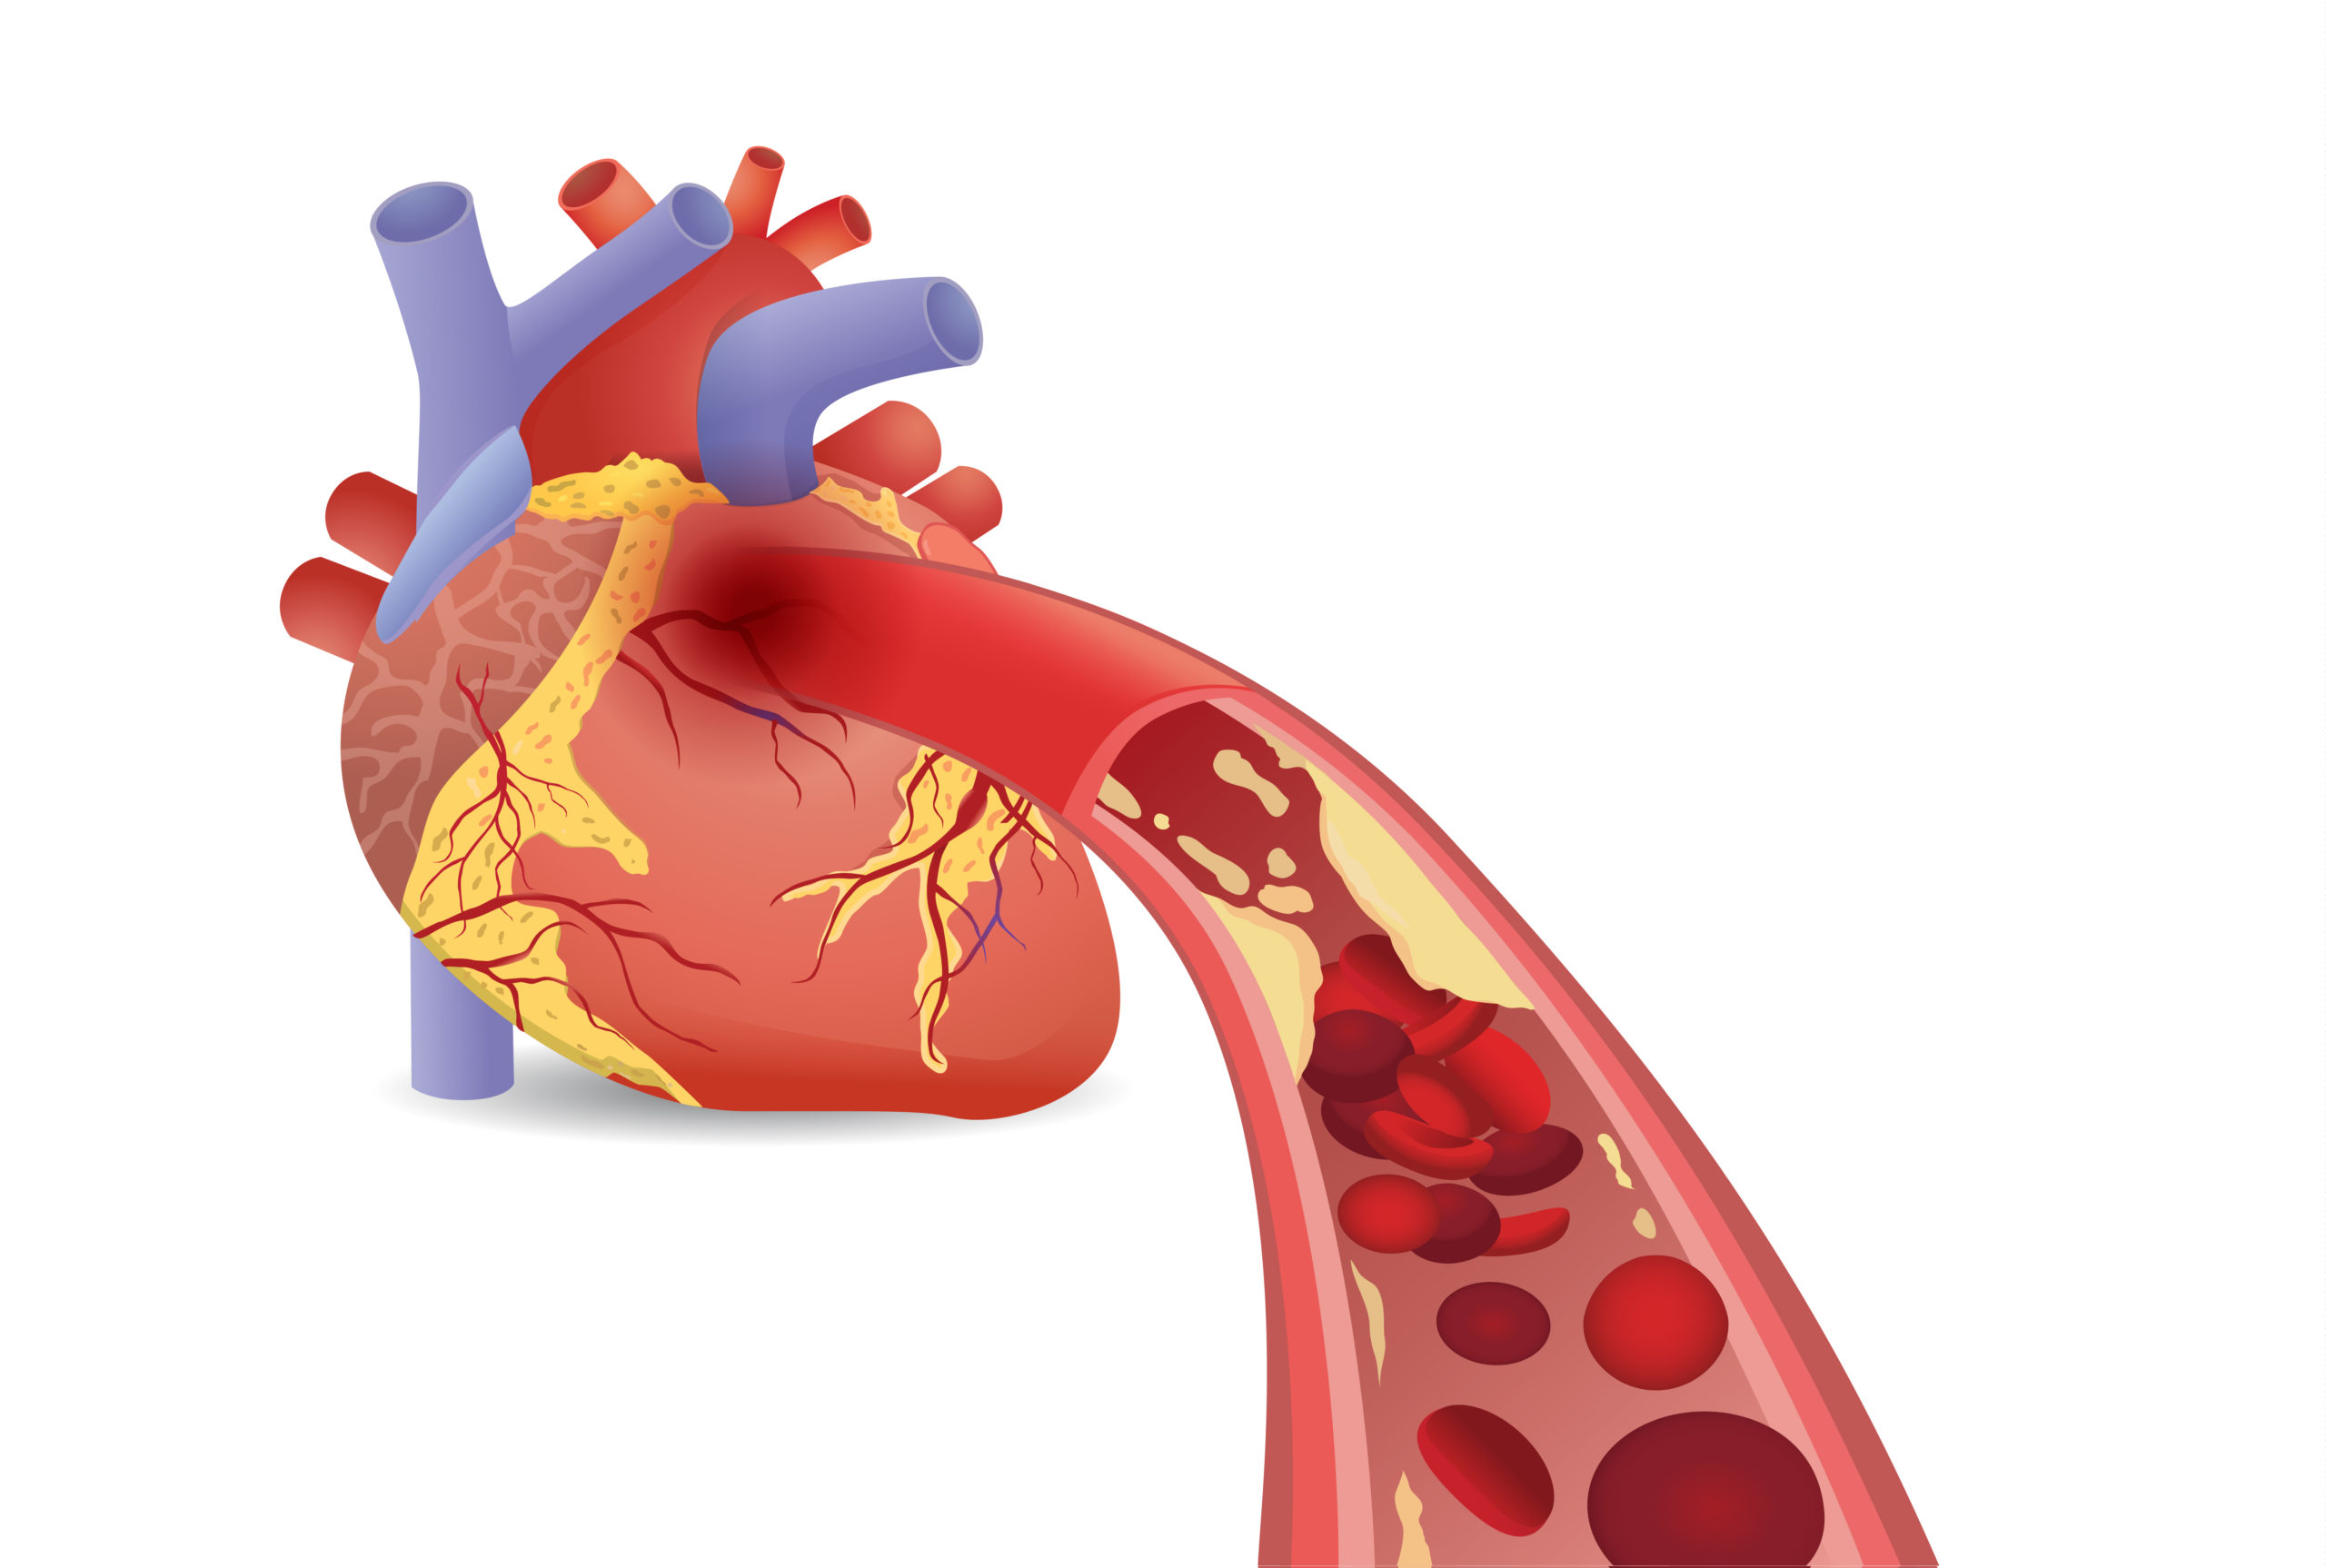

In patients with atrial fibrillation and coronary artery disease (CAD), researchers found that rivaroxaban monotherapy ...

In the BASKET-SMALL 2 randomized controlled trial, researchers compared the effect of a drug-coated balloon (DCB) ...

Researchers in the Netherlands aimed to illuminate the clinical and economic effects of treatment with rivaroxaban from ...

A study presented at the Transcatheter Cardiovascular Therapeutics (TCT) 2021 Annual Meeting investigated long-term ...

A pooled analysis of randomized trials found that moderate to severe coronary artery calcification (CAC) is associated ...

Coronary computed tomography angiography (CCTA) can detect atherosclerosis, even among individuals with no coronary ...

The results of a study show a link between the profile of serum fatty acids (FAs) and early-onset coronary artery ...